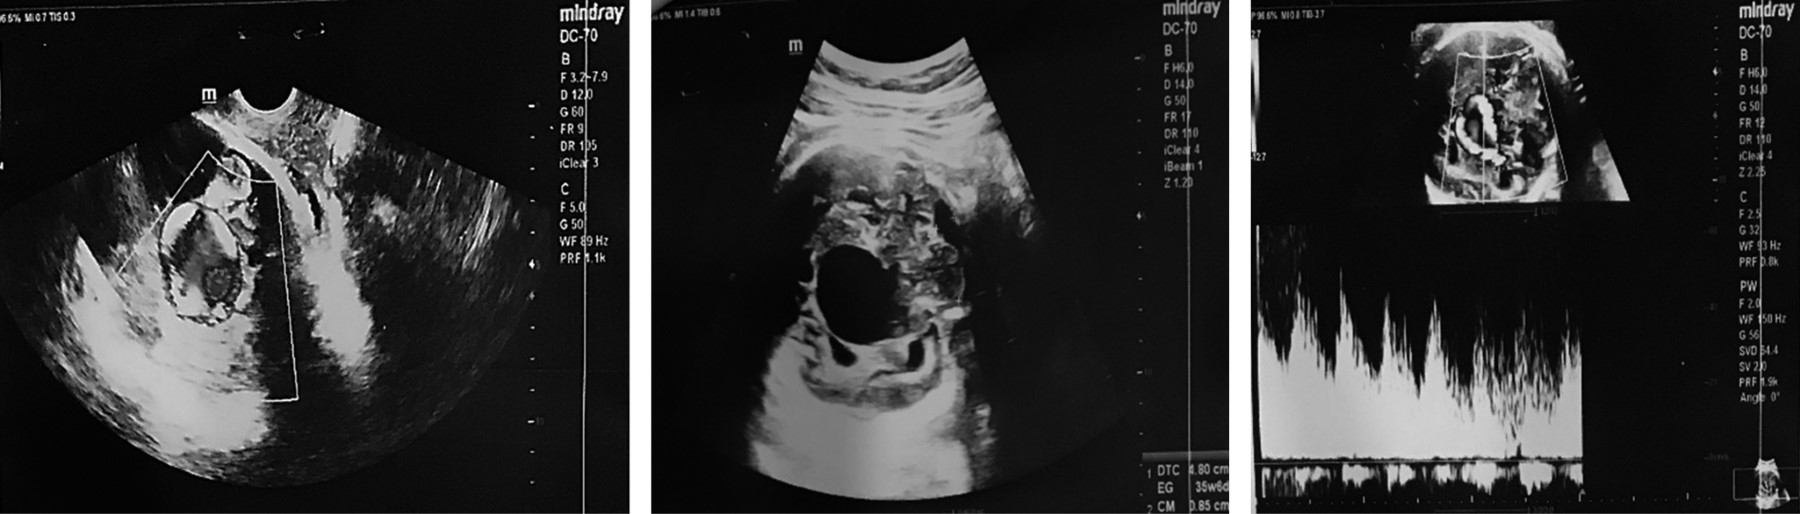

RN masculino, primer producto de una madre de 19 años. A las 25 semanas de gestación (SDG), por ecografía gestacional, se identificó un hematoma supratentorial. Mientras que a las 33.6 SDG, por sospecha de holoprosencefalia se realizó una neurosonografía fetal, en la cual se encontró imagen anecoica en forma de reloj de arena, de dimensiones de 74 × 37 mm, vascularizada, sugestiva de malformación venosa tipo aneurisma de la vena de Galeno (Figura 1). A las 35 SDG por ecocardiografía se detectó cardiomegalia con sobrecarga de cavidades derechas.

Figura 1